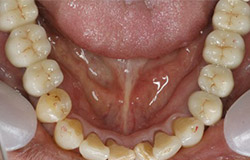

インプラントで噛み合わせの再構成を伴った症例。

治療後のメンテナンスを行わないと

周囲炎になるリスクあり。